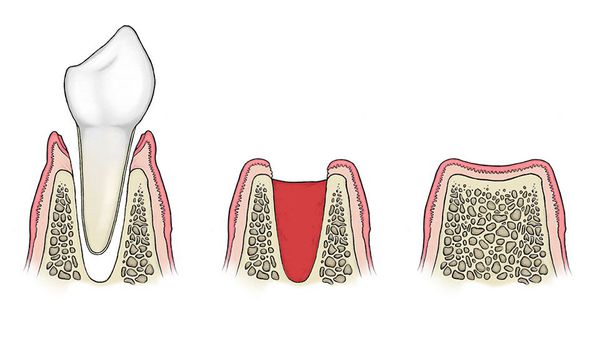

Po usunięciu zęba w zębodole tworzy się skrzep krwi, który pełni rolę naturalnego opatrunku – chroni ranę przed zakażeniem i stanowi podstawę do jej prawidłowego gojenia. Skrzep osłania odsłoniętą kość, zabezpiecza zakończenia nerwowe oraz umożliwia stopniową odbudowę tkanek od wewnątrz.

Prawidłowy proces gojenia przebiega etapowo:

- Bezpośrednio po zabiegu – pod wpływem trombiny i fibrynogenu tworzy się skrzep krwi, który szczelnie wypełnia zębodół;

- Po kilku godzinach – na jego powierzchni zaczynają się namnażać komórki nabłonka dziąsła;

- W kolejnych dniach – do wnętrza skrzepu wrastają nowe naczynia krwionośne z otaczającej kości, dostarczając składniki odżywcze i tlen;

- W dalszej fazie – skrzep stopniowo się rozpuszcza, a jego miejsce zajmuje młoda tkanka kostna, która z czasem ulega mineralizacji.

Skrzep krwi jest więc strukturą tymczasową, ale niezbędną dla rozpoczęcia procesu regeneracji. Jego utrata lub rozpad prowadzi do odsłonięcia kości, co uniemożliwia gojenie i może doprowadzić do rozwoju zapalenia zębodołu.

W przypadku alweolitis proces rozpuszczania skrzepu krwi, czyli fibrynoliza, przebiega zbyt szybko. W rezultacie skrzep rozpada się przedwcześnie, a zębodół pozostaje odsłonięty i pozbawiony ochrony, co prowadzi do rozwoju stanu zapalnego oraz silnego bólu.